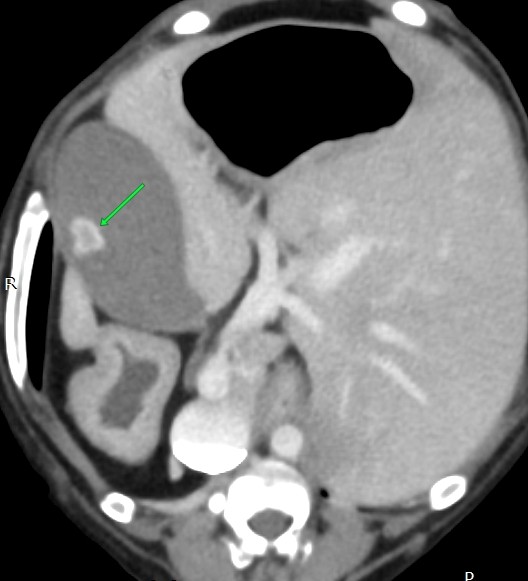

腫瘍を疑い手術ですので、術前にCT検査です

①脾臓の腫大

③胆石あり

①は転移の可能性もあるので手術時に脾臓の細胞検査